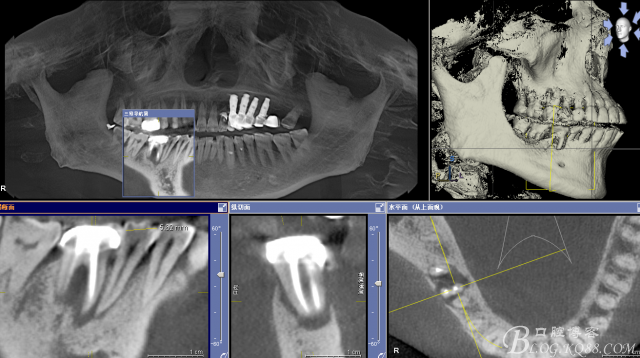

CT可見根管內有白色顯影物和根周較大暗影

從根管影像看治療還是不錯的,

懷疑牙根微裂,

所以建議患者手術探查

三維檢查種植體位置,方向,平行度